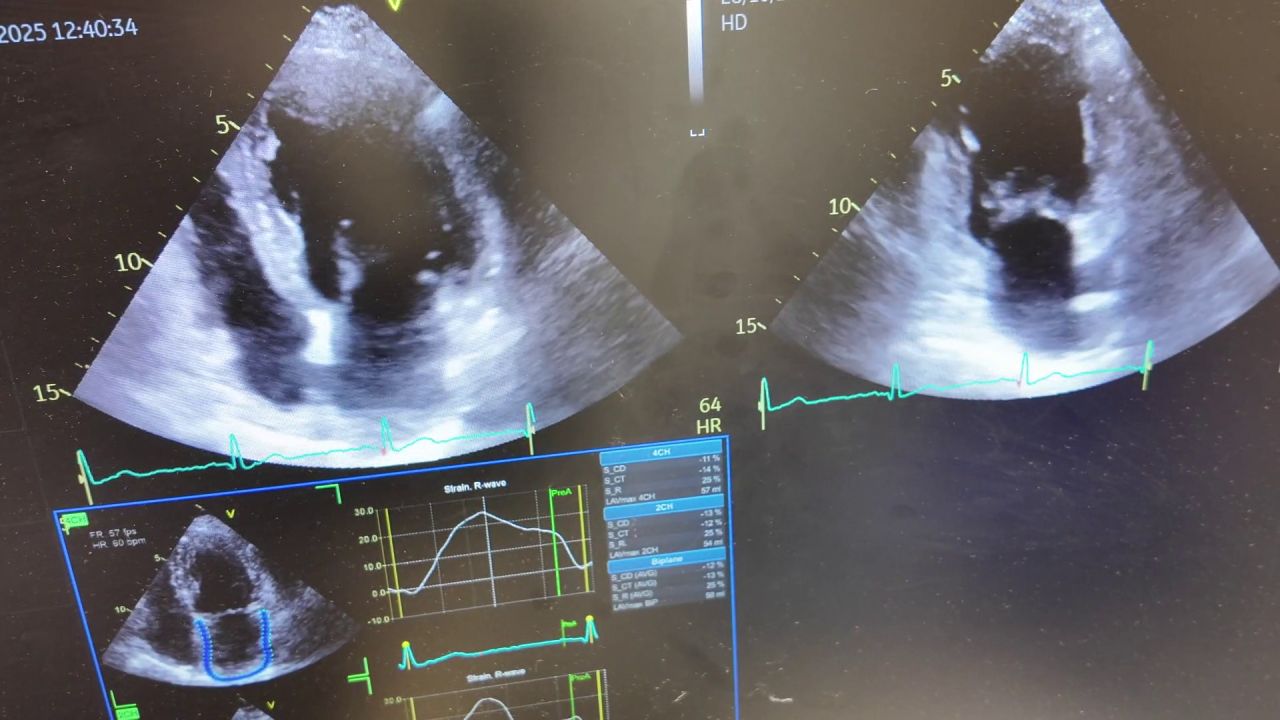

Pacjenci kardiologiczni skorzystają na KPO. Szpital w Jaworznie zakupi nowoczesne urządzenia

Wideo: Pacjenci kardiologiczni skorzystają na KPO. Szpital w Jaworznie zakupi nowoczesne urządzenia